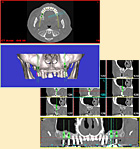

インプラントを入れる部位の顎の骨の検査をします(CT撮影)。 このCTスキャンのデータをコンピュータ上で立体画像として解析し、骨の詳しい厚みや、高さ、形状を診査し、最適な形状のインプラントを選択します。 |